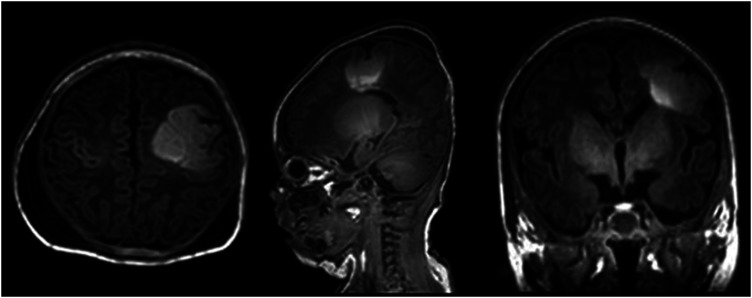

We describe a neonate presenting on first day of life with refractory seizures secondary to a single, large area of focal cortical dysplasia (FCD) who underwent surgical resection at age 3 weeks leading to resolution of seizure activity and dramatic improvement in developmental trajectory. Surgical intervention for epilepsy is infrequently offered for neonates, often reserved only for those with catastrophic presentations. This case demonstrates that surgical intervention can be safe and efficacious in neonates for pharmaco-resistant seizures associated with a focal lesion. Rapid whole exome sequencing in this case yielded a germline novel de novo TSC1 mutation, leading to a genetic diagnosis of tuberous sclerosis complex (TSC). Our patient demonstrates an atypical neonatal presentation of TSC. Limited data is available for those with isolated FCD in TSC; this is the first reported case in a neonate.